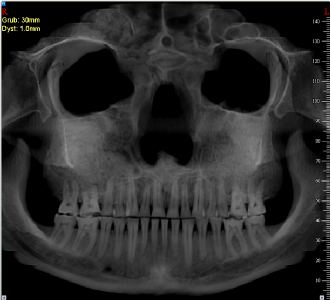

To właśnie doskonale zachowana czaszka „Wojownika” stała się pretekstem do nawiązania współpracy z zespołem badawczym dr Doroty Lorkiewicz-Muszyńskiej z Katedry i Zakładu Medycyny Sądowej Uniwersytetu Medycznego w Poznaniu. Początkowo planowano jedynie wykonanie rekonstrukcji twarzy. Zakres analiz jednak zdecydowanie poszerzono. W trakcie ostatnich lat poza oczywistymi badaniami antropologicznymi, wykonano serię dodatkowych analiz także przy użyciu tomografii komputerowej i rezonansu magnetycznego. Pozwoliły one między innymi wskazać na zmiany w materiale kostnym o charakterze degeneracyjnym. Interesujące było odkrycie w kości piszczelowej – łagodnej, być może bezobjawowej postaci nowotworu - kostniaka śródkostnego. Wyniki badań z tomografii były z kolei bazą do wykonywania trójwymiarowej kopii czaszki metodą druku przestrzennego (drukarki 3D). Tomografia komputerowa czaszki posłużyła również do wykonania modelu twarzy, a ten z kolei został wykorzystany przez artystę-rzeźbiarza, celem wykonania modelu z gliny. Końcowym efektem tego procesu, będzie wykonanie pełno postaciowego manekina, o budowie fizycznej i rysach twarzy odtworzonych na podstawie przeprowadzonych analiz. Indywidualne cechy takie jak włosy, broda, czy zmarszczki dostoswane będą do szacowanego wieku Wojownika. Postać ta, wyposażona w rekonstrukcje odkrytych w grobie przedmiotów, stanie się jednym z podstawowych elementów ekspozycji.

Oddzielnym analizom poddane zostały zęby wszystkich osobników odkrytych na cmentarzysku w Rogalinie (ryc.6). Pozwoliły one m.in. na określenie wieku zębowego, oraz na zaobserwowanie skali zmian patologicznych takich jak próchnica. Łącznie przebadano niemal 200 zębów. Szczególnie intersujące są spostrzeżenia dotyczące pochówku nr 4, w którym znaleziono zęby z próchnicą. Zaawansowane stadium zmian, sięgnęło komory zęba i kanałów korzeniowych, powodując z pewnością bardzo bolesne zakażenie, natomiast infekcja rozszerzająca się tą drogą do otaczającej kości mogła być nawet przyczyną śmierci. Badaniami kierowała dr Agnieszka Przystańska.